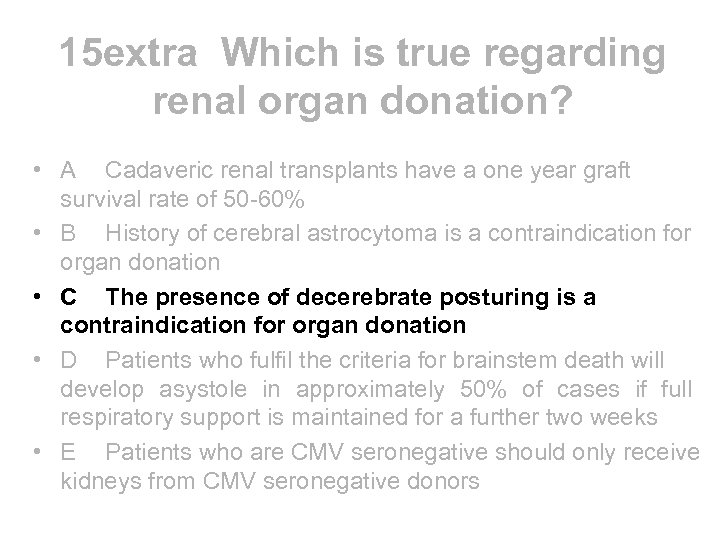

15 extra Which is true regarding renal organ donation? • A Cadaveric renal transplants have a one year graft survival rate of 50 -60% • B History of cerebral astrocytoma is a contraindication for organ donation • C The presence of decerebrate posturing is a contraindication for organ donation • D Patients who fulfil the criteria for brainstem death will develop asystole in approximately 50% of cases if full respiratory support is maintained for a further two weeks • E Patients who are CMV seronegative should only receive kidneys from CMV seronegative donors

15 extra Which is true regarding renal organ donation? • A Cadaveric renal transplants have a one year graft survival rate of 50 -60% • B History of cerebral astrocytoma is a contraindication for organ donation • C The presence of decerebrate posturing is a contraindication for organ donation • D Patients who fulfil the criteria for brainstem death will develop asystole in approximately 50% of cases if full respiratory support is maintained for a further two weeks • E Patients who are CMV seronegative should only receive kidneys from CMV seronegative donors

15 extra Which is true regarding renal organ donation? • A Cadaveric renal transplants have a one year graft survival rate of 50 -60% • B History of cerebral astrocytoma is a contraindication for organ donation • C The presence of decerebrate posturing is a contraindication for organ donation • D Patients who fulfil the criteria for brainstem death will develop asystole in approximately 50% of cases if full respiratory support is maintained for a further two weeks • E Patients who are CMV seronegative should only receive kidneys from CMV seronegative donors

15 extra Which is true regarding renal organ donation? • A Cadaveric renal transplants have a one year graft survival rate of 50 -60% • B History of cerebral astrocytoma is a contraindication for organ donation • C The presence of decerebrate posturing is a contraindication for organ donation • D Patients who fulfil the criteria for brainstem death will develop asystole in approximately 50% of cases if full respiratory support is maintained for a further two weeks • E Patients who are CMV seronegative should only receive kidneys from CMV seronegative donors

Transplant preparation • Recipient work up • - must be free of vascular disease, malignancy and infection • - only indications for nephrectomy before transplant are uncontrolled hypertension, pyonephrosis and significant recurrent UTI (no indication to remove chronic pyelo kidneys per se) • Donor work up • - Cadaveric donors who fulfil criteria for brain stem death will develop asystole within days of diagnosis. Decerebrate posturing is a sign of neuronal activity ie does not fulfil criteria • - must have no evidence of malignancy except 1 y brain tumours, or BCC/SCC with no recurrence 5 years after treatment • - must be HBV, HCV, HIV negative. Can be CMV positive higher incidence of CMV disease if CMV+ kidney given to CMVdonor but this combination is not a contraindication to Tx

Transplant preparation • Recipient work up • - must be free of vascular disease, malignancy and infection • - only indications for nephrectomy before transplant are uncontrolled hypertension, pyonephrosis and significant recurrent UTI (no indication to remove chronic pyelo kidneys per se) • Donor work up • - Cadaveric donors who fulfil criteria for brain stem death will develop asystole within days of diagnosis. Decerebrate posturing is a sign of neuronal activity ie does not fulfil criteria • - must have no evidence of malignancy except 1 y brain tumours, or BCC/SCC with no recurrence 5 years after treatment • - must be HBV, HCV, HIV negative. Can be CMV positive higher incidence of CMV disease if CMV+ kidney given to CMVdonor but this combination is not a contraindication to Tx

Post transplantation • • • Graft survival - cadaveric graft survival rates >90% at one year now expected - patient can have up to 3 further tx if graft fails Anti rejection therapy - all require immunosuppression except identical twins (haploidentical simply means they have inherited the same HLA and DR antigens from parents, not that they are identical twins) - most now start with prednisolone, tacrolimus and mycophenolate Cancer risk - skin cancers are most common malignancy. SCC>BCC which is reverse of that seen in gen pop. Solar keratoses are premalignant - post transplant lymphoproliferative disorder (PTLD) can occur at any stage post transplant and is often assoc with EBV - other cancers incl breast, cervix, colon - women should have annual smear

Post transplantation • • • Graft survival - cadaveric graft survival rates >90% at one year now expected - patient can have up to 3 further tx if graft fails Anti rejection therapy - all require immunosuppression except identical twins (haploidentical simply means they have inherited the same HLA and DR antigens from parents, not that they are identical twins) - most now start with prednisolone, tacrolimus and mycophenolate Cancer risk - skin cancers are most common malignancy. SCC>BCC which is reverse of that seen in gen pop. Solar keratoses are premalignant - post transplant lymphoproliferative disorder (PTLD) can occur at any stage post transplant and is often assoc with EBV - other cancers incl breast, cervix, colon - women should have annual smear